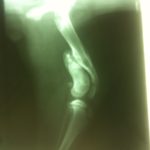

She had a pronounced limp and on performing x-rays our veterinarian found that the femur has grown a long spike that had extended and was now impinging on the knee cap in the attempt to ‘close the space’. Vale was in a great deal of pain from this and the vet performed a surgery to cut the point off, re-break the bone, and plate the fracture so it will heal (and hopefully grow) properly. The plate may have to be removed in about three months, so Vale is not really available for adoption until we know if the plate will stay or not.